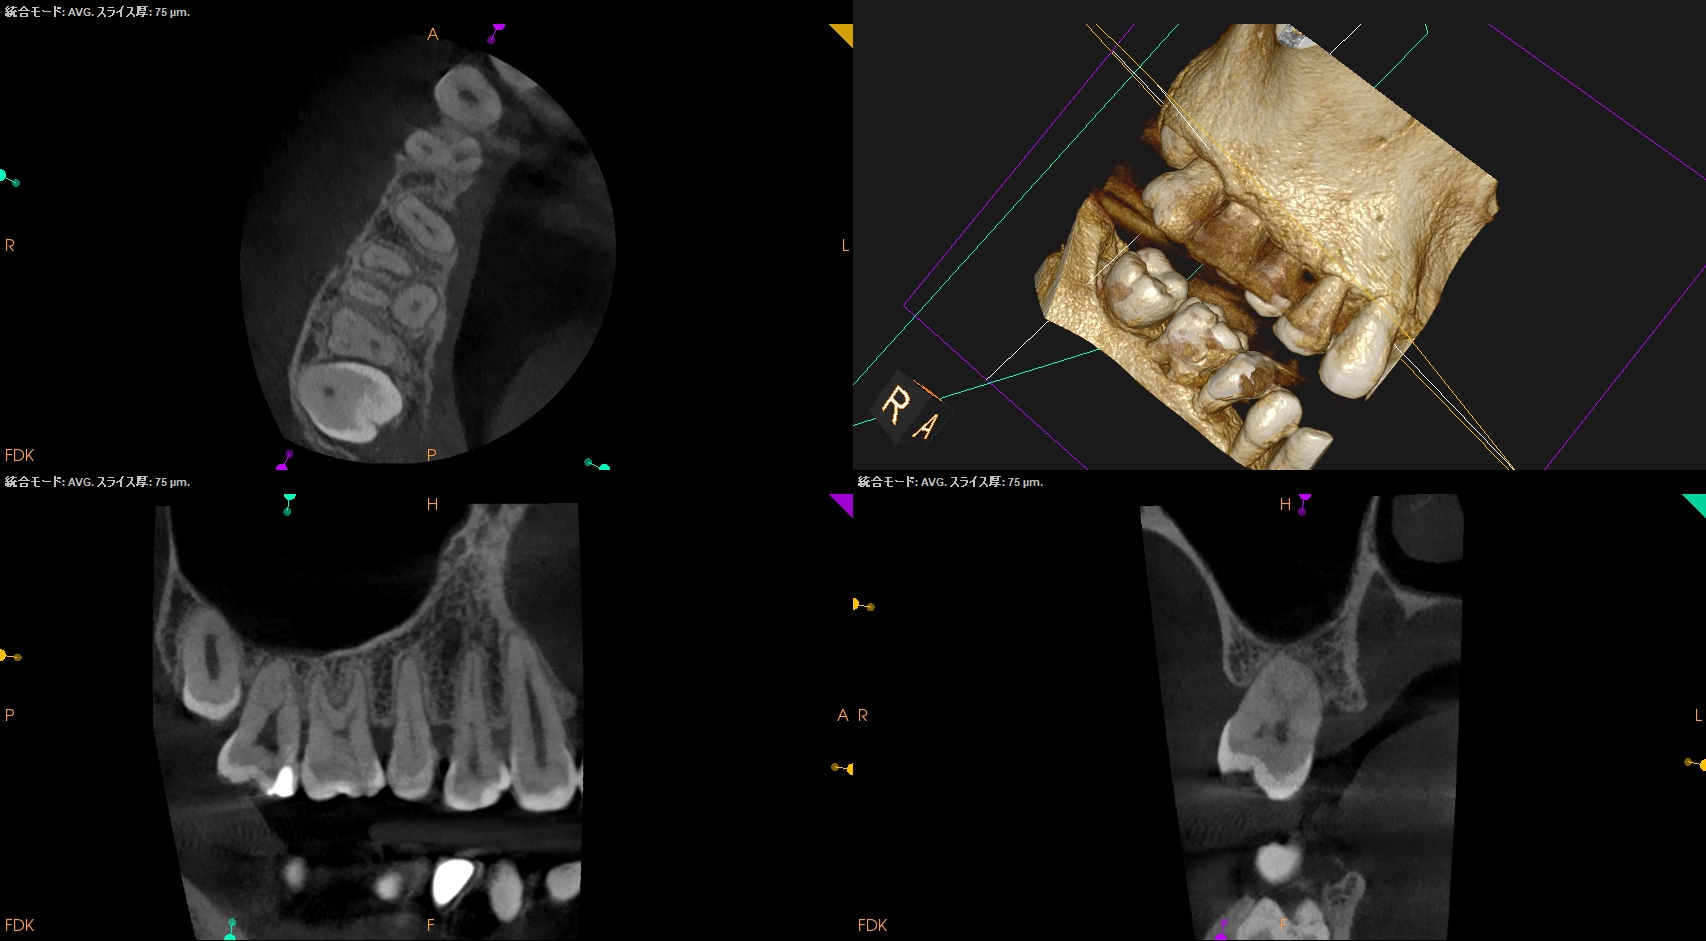

この治療から1.9yr経過していた。

#14 Intentional Replantation 1.9yr recall(2026.1.6)

術前のSinus tractは消失した。

Sinus tractの消失は問題解決の“証拠”である。

初診時と比較した。

問題が劇的に解決していることがわかる。

また、最終補綴も既に装着されていることからこの日で終診とさせていただいた。